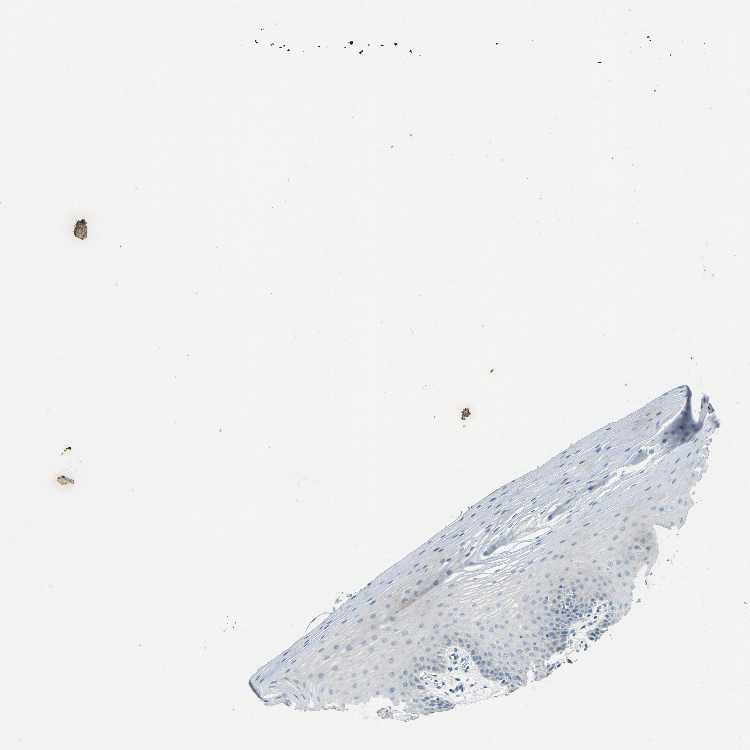

TISSUE PRIMARY DATA ORAL MUCOSA Show tissue menu

ORAL MUCOSA - Antibody stainingi

Antibody staining in the annotated cell types in the current human tissue is reported as not detected, low, medium, or high, based on conventional immunohistochemistry profiling in selected tissues. This score is based on the combination of the staining intensity and fraction of stained cells.

Each image is clickable and will lead to virtual microscopy that enables deeper exploration of all samples and also displays staining intensity scores, fraction scores and subcellular localization as well as patient and tissue information for each sample.

Antibody HPA014377

Squamous epithelial cells Not detected